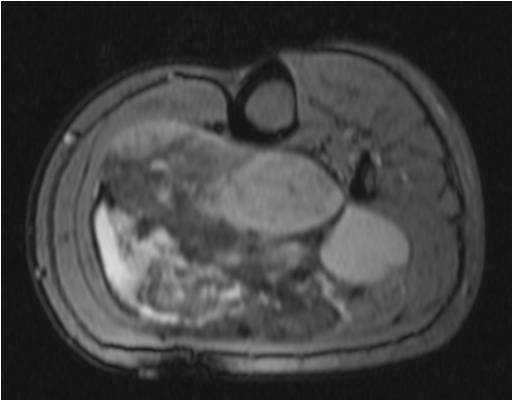

On radiographs, Low Grade Fibromyxoid Sarcoma presents as a discrete mass with soft tissue density without mineralization. MRI shows a well circumscribed heterogeneous mass, primarily hypo or isointense to muscles on T1-weighted image. The majority of tumors demonstrate heterogeneous signal intensity on T2-weighted images, correlating with the histological characteristics of low grade fibromyxoid sarcoma. Although 48 % of the patients demonstrate hyperintense signal and the rest of patients present admixed of hypo and Isointense signals (Fig. 1-5).

Fig. 3-5. MRI Axial (Fig. 3) and Coronal (Fig. 4) T2 –weighted fat-suppressed image heterogeneously high signal intensity areas admixed with hypo and isointense areas. T1-weighted post contrast fat-suppressed images (Fig. 5) show heterogeneous signal and enhancement within the tumor.